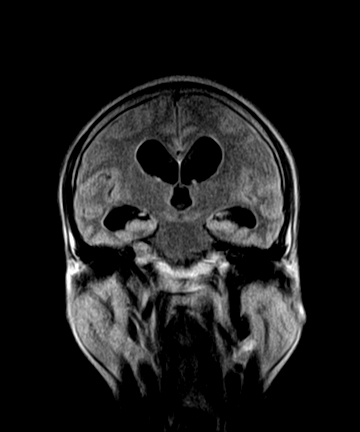

标题: MRI2064:少见病例。男性52,视力下降多年。 [打印本页]

标题: MRI2064:少见病例。男性52,视力下降多年。

四脑室区见混杂信号占位影,脑室系统扩张明显,临近结构显著受压称位,患者52岁,多考虑室管膜瘤可能性大

考虑第四脑室室管膜瘤并阻塞性脑积水。

考虑第四脑室室管膜瘤并梗阻性脑积水;部分性空蝶鞍;左侧上颌窦粘膜下囊肿。

考虑第四脑室室管膜瘤【血供丰富血管母细胞瘤可能】并梗阻性脑积水;部分性空蝶鞍;左侧上颌窦粘膜下囊肿。

比较典型的脉络丛乳头状瘤并脑积水,鉴别小脑蚓部血管母细胞瘤。